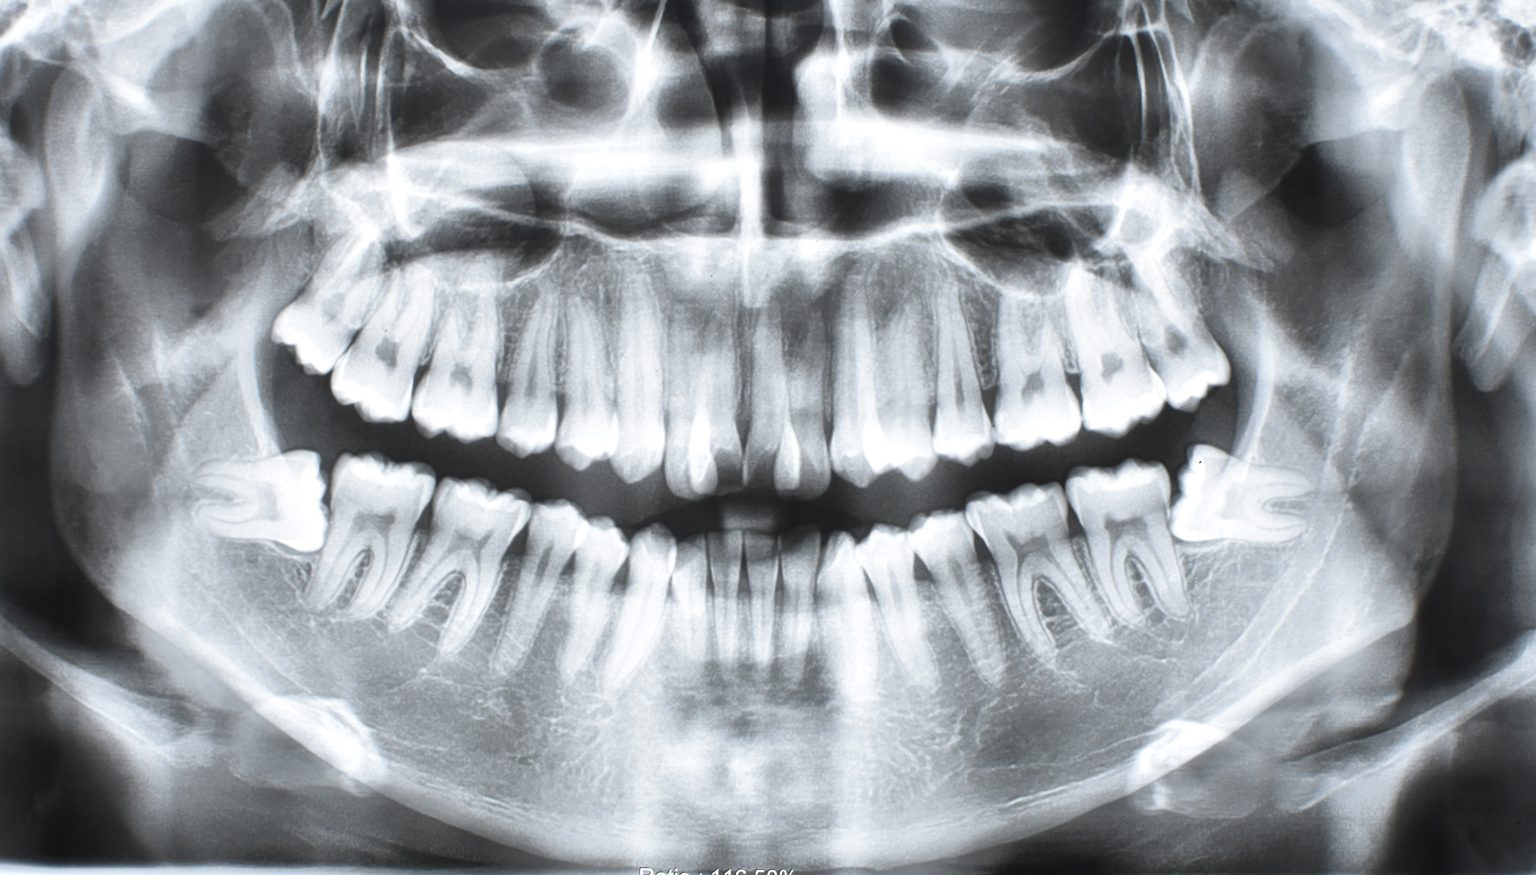

Canino retenido / Maxilar sin desarrollo completo

Paciente de 18 años con canino retenido (entre paladar y piso de fosas nasales) y maxilar sin desarrollo completo.

Se hace valoración Ortodontica con tomografía, para hacer cirugía de sutura palatina. Esta se descarta y se realiza disyunción con Orto implantes.